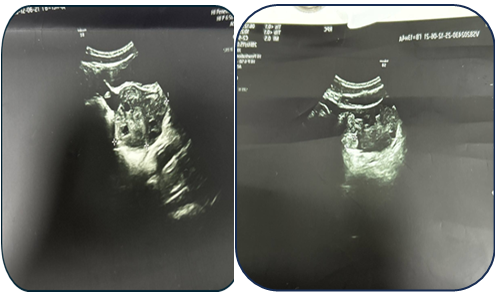

Case 1: A 17-year-old female presented with acute pain. Ultrasound revealed a 95 mm complex left ovarian cyst with no Doppler flow (Fig. 1). Emergency laparoscopy confirmed a 720-degree torsion. Detorsion and cystectomy were performed. Intraoperative findings are shown in Fig. 2, Fig. 3, and Fig. 4. Histopathology reported a serous cystadenoma. Postoperative ultrasound on day 5 confirmed a viable ovary (Fig. 5). | Figure 1. Ultrasound findings of a left ovarian cyst with torsion |

| Figure 5. Postoperative ultrasound examination on day 5 |

Case 2: An 11-year-old female presented with a torsed, edematous left ovary (69x49 mm) on ultrasound (Fig. 6). Laparoscopic detorsion alone was performed (Fig. 7 & Fig. 8). Serial postoperative ultrasounds documented the gradual resolution of edema and the return of vascularity by day 20 (Fig. 9), confirming ovarian recovery. | Figure 6. Preoperative ultrasound examination of the left ovary |

| Figure 9. Ultrasound examination on postoperative day 20 |